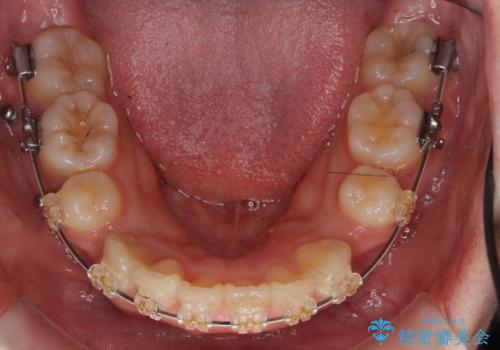

- 矯正装置

- 審美装置

上下左右の小臼歯を抜歯しています。